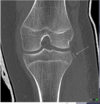

Fratura do platô tibial lateral - Schatzker tipo 2 (traço de fratura + depressão do plato lateral).